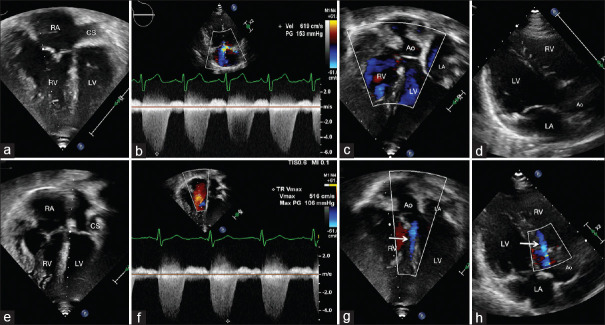

This hemodynamic round section deals with severe pulmonary arterial hypertension with suprasystemic pulmonary artery pressures in a patient who underwent delayed surgical correction of the double-outlet right ventricle with a large subaortic ventricular septal defect (VSD). Recreation of a moderate-sized VSD by electrocautery-aided fenestration of the surgical patch resulted in effective right ventricular decompression. The changes in the hemodynamics are illustrated in the pressure traces and Doppler echocardiographic images. The changes in cardiac events on the right and left heart due to the right bundle branch block are also illustrated in the manuscript.